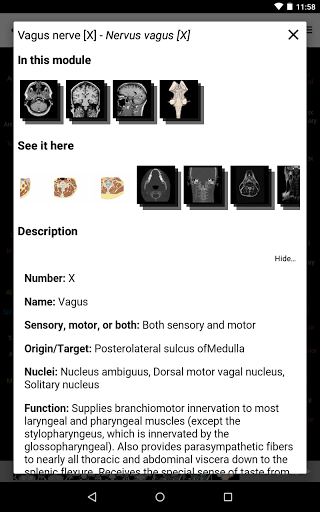

*Improved detail view of anatomical parts for easier identification in images of the current and other modules.

*Improved visibility of anatomical parts definitions

*Browse between anatomical parts using description links

-In the details view of an anatomical structure related terms are now displayed